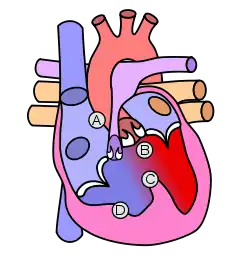

Tetralogy of Fallot results in low oxygenation of blood. This is due to a mixing of oxygenated and deoxygenated blood in the left ventricle via the ventricular septal defect (VSD) and preferential flow of the mixed blood from both ventricles through the aorta because of the obstruction to flow through the pulmonary valve. The latter is known as a right-to-left shunt.[17]

Embryology studies show that anterior malalignment of the aorticopulmonary septum results in the clinical combination of a ventricular septal defect (VSD), pulmonary stenosis, and an overriding aorta.[20]: 200 Right ventricular hypertrophy develops progressively from resistance to blood flow through the right ventricular outflow tract.[10]

Pathophysiology

In healthy individuals, the human heart develops around the 20th day of gestation, when the outer endocardial tubes merge into a single cardiac tube. Thereafter, the cardiac tube begins to fold, developing into the atrium and ventricle. The right ventricle is dominant prior to birth, receiving 65% of the venous return to the heart, and is the main contributor of blood flow to the lower part of the body, the placenta, and the lungs. Though the exact cause of TOF is unknown, an association that has been observed is an anterior deviation of the infundibular septum that results in a misaligned VSD, with an overriding aorta causing a subsequent right ventricular obstruction.[9]

Different factors such as pulmonary stenosis can also contribute with the right ventricular outflow obstruction. During tet spells, a decrease in systemic vascular resistance or an increase in pulmonary resistance would be physiologically observed.

The main anatomic defect in TOF is the anterior deviation of the pulmonary outflow septum.[10] This defect results in narrowing of the right ventricular outflow tract (RVOT), override of the aorta, and a VSD.[40]